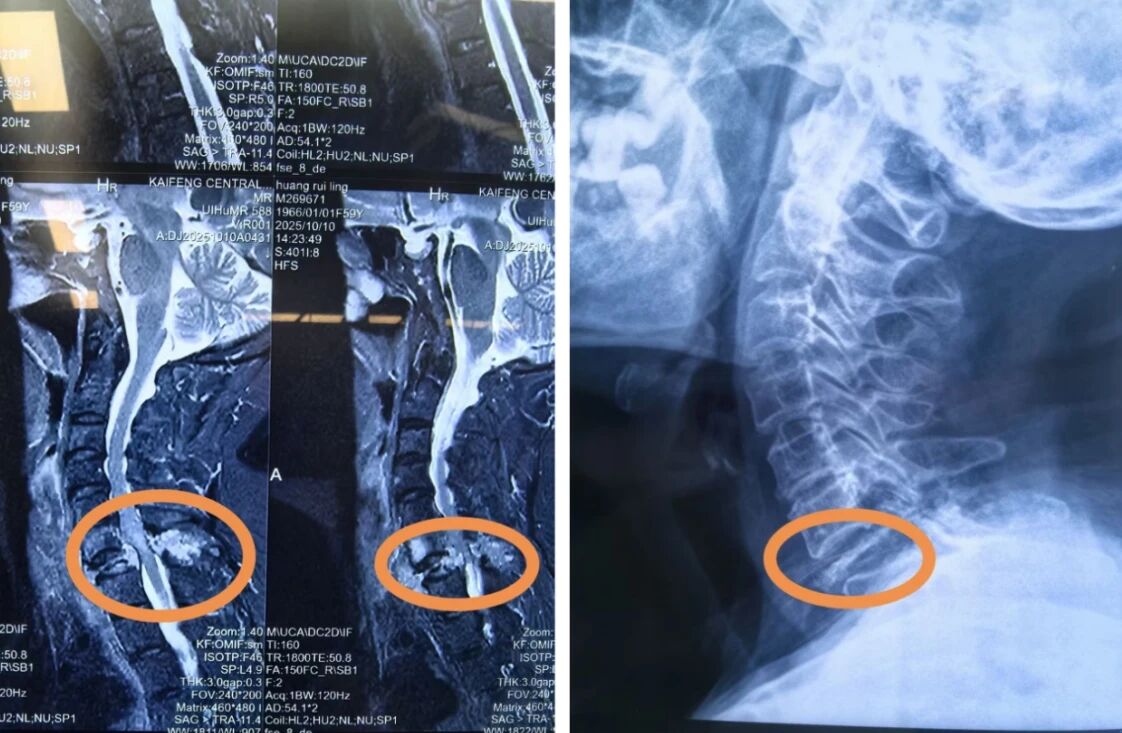

术前的核磁示:颈7椎体及附件区可见肿瘤侵犯信号

颈椎DR示:第7颈椎椎体明显破坏并压缩